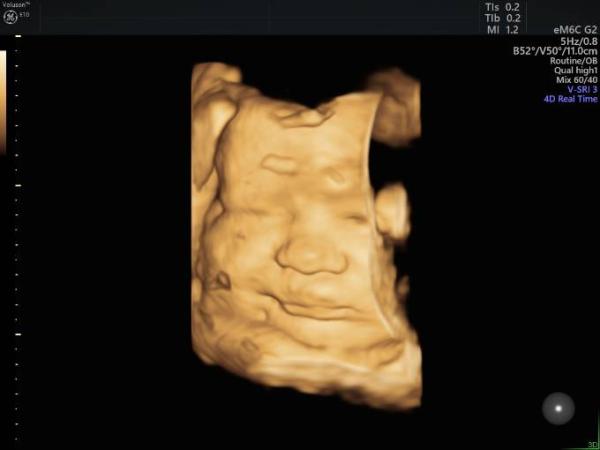

es gab sogar 2 Fotos :)

Bild zu